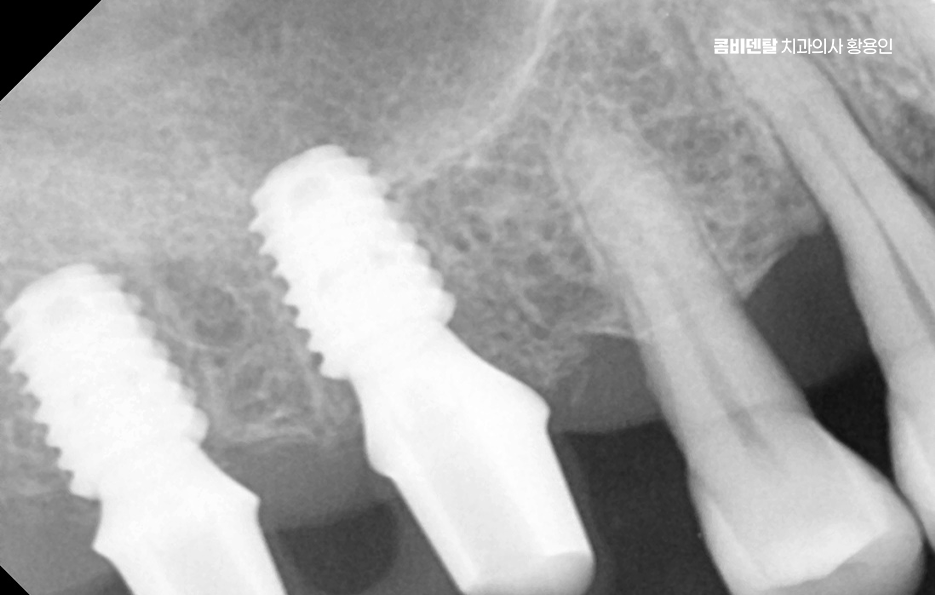

임플란트는 턱뼈 안에 임플란트의 고정체(인공치근)를 식립해서 치아를 대신하는 구조로 이 고정체가 제대로 자리를 잡고 버텨주려면 최소한의 잇몸뼈 높이와 넓이, 골질이 확보돼 있어야 안정성이 확보되는 거예요. 그런데 이 뼈가 부족한 상태에서 임플란트 뼈이식 안하면 그리고 억지로 임플란트를 심게 되면 어떤 일이 생기냐면, 첫째로 임플란트가 제대로 뼈와 붙지 못해서 탈락하거나 흔들릴 가능성이 높고 둘째로는 식립 부위 주변의 잇몸이 꺼지면서 심미적으로도 부자연스러운 결과를 낳을 수 있어요

잇몸뼈는 자연치아를 잃고 나면 시간이 지남에 따라 서서히 흡수되는데 특히 상실한 치아를 오랫동안 방치한 경우에는 뼈가 눈에 띄게 줄어드는 일이 흔하고, 치주염이나 염증이 반복된 경우에도 주변 골조직이 녹아내려 뼈의 두께와 높이가 부족해지게 되는데 이런 상태에서 임플란트 뼈이식 안하면 그리고 임플란트를 바로 심는다면, 뼈의 지지력이 부족하기 때문에 인공치근이 쉽게 움직이거나 주변에 염증이 생겨 골융합이 제대로 되지 않게 되고 결국엔 수개월 후에 탈락하거나 실패하게 되는 일이 생길 수 있는 거예요.

그렇다면 뼈이식을 언제, 어떻게 계획해야 하는지가 중요한데 첫 번째는 임플란트 식립 전 단계에서 충분한 영상 진단과 분석을 통해 뼈의 양과 질을 정밀하게 평가해야 하며 단순 파노라마 X-ray만으로는 확인이 어려운 입체적인 골량이나 신경과의 거리, 부비동 위치 등을 정확히 파악하려면 3D CT 촬영이 필수적이고 이를 통해 상악동 거상술이 필요한지 등을 판단할 수 있어요.

두 번째는 뼈이식을 단독으로 먼저 시행할 것인지, 임플란트 식립과 동시에 병행할 것인지를 결정해야 하는데 뼈 소실 정도가 심하지 않은 경우라면 동시에 진행할 수도 있지만, 뼈가 너무 얇거나 신경과 가까운 부위라면 3~6개월 정도의 치유기간을 두고 뼈이식만 먼저 시행한 뒤, 뼈가 자리 잡은 후에 임플란트를 식립하는 2단계 방식이 안전한 선택이 되는 거예요.